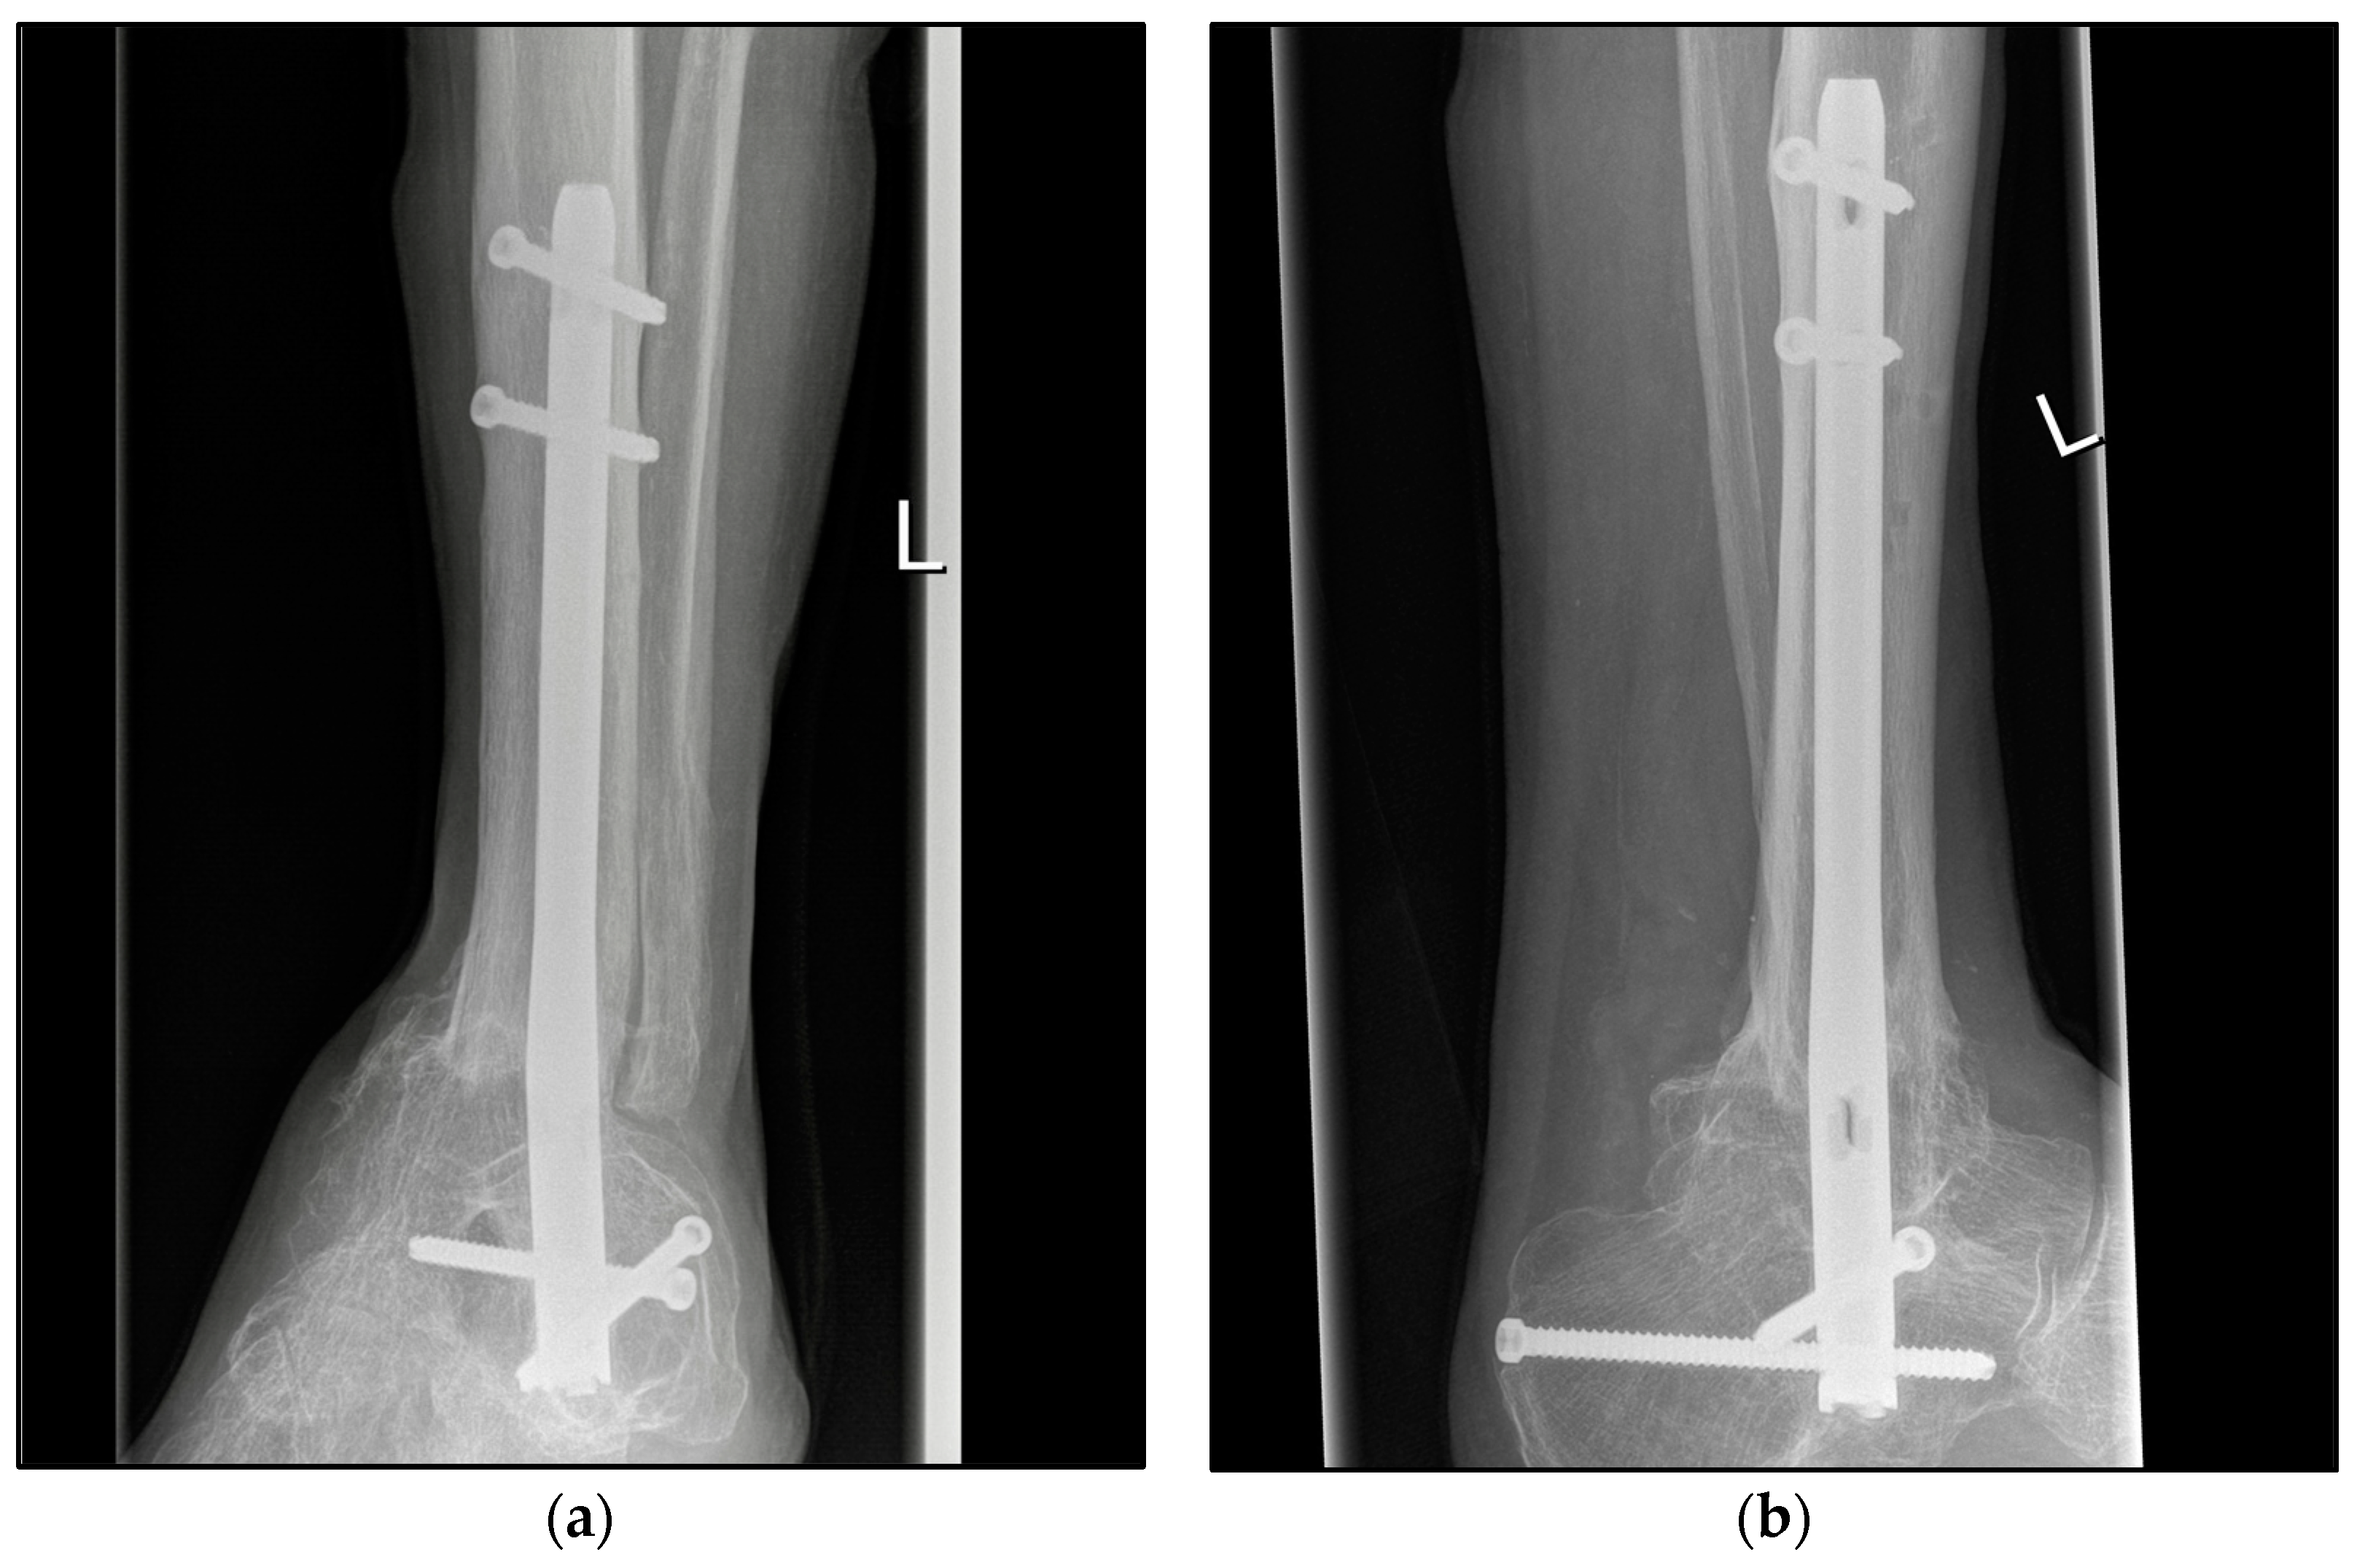

Figure 4.

Postoperative radiographic findings of end-stage posttraumatic arthritis of the left ankle with septic history of a 82-year-old male treated with a tibiotalocalcaneal arthrodesis T2™ Ankle Arthrodesis Nail, 200 × 10 mm. (a,b) Anteroposterior and lateral view; view, 5 years post operation.